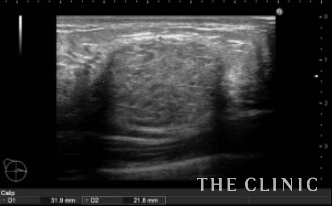

2年前に他院にて片側300㏄ずつの脂肪注入を受けられています。注入後、間もなくしこりを感じるようになり、今回はしこり除去の目的で当院を受診されました。右胸にはオイルシストと充実性のしこり、左胸には47.3㎜の充実性のしこりを認めました。(オイルシストの症例はNo.24でご紹介します)

充実性のしこりはベイザーリポで脂肪を崩して吸引します。ポイントはしこりの被膜内のみにベイザーをかけて、確実に吸引することです。

左)吸引後、しこりは消失しました。右)吸引した壊死している脂肪です。